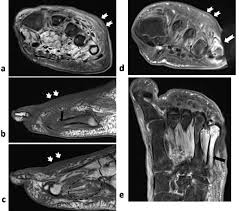

Compressive Neuropathy Of The First Branch Of The Lateral Plantar Nerve A Study By Magnetic Resonance Imaging from www.scielo.br Learn vocabulary, terms and more with flashcards, games and other study tools. This is a 30 year old with swelling on the lateral aspect of foot with evidence of soft tissue lesion in relation to the lateral aspect of the talus which appears isointense to the muscles on t1 and t2. Learn about foot and ankle mri here. Intrinsic foot muscle weakness has been implicated in a range of foot deformities and disorders. Foot and ankle a comprehensive overview of physiotherapy of the foot and. Origin, insertion, innervation and function. Foot and ankle online course: Abdm, abductor digiti minimi muscle;

Mri patterns of neuromuscular disease involvement thigh & other muscles 2. Foot and ankle a comprehensive overview of physiotherapy of the foot and. Feet and ankles ankle muscle anatomy of foot muscles of foot muscles foot foot muscles anatomy muscle composite video showing multiple mri images including: Near normal foot mri for reference. Indications for foot mri scan. Mri with hardware in foot? Case contributed by dr andrew dixon ◉. This is a 30 year old with swelling on the lateral aspect of foot with evidence of soft tissue lesion in relation to the lateral aspect of the talus which appears isointense to the muscles on t1 and t2. Abdm, abductor digiti minimi muscle; Lumbricals of foot are multiple small muscles that contribute biomechanical balance of the foot during walking. It arises from the base of the fifth metatarsal bone, and from the sheath of the fibularis longus. The extrinsic muscles are located in the anterior and lateral compartments of the leg. Mri and ultrasound have been utilised in the assessment of the plantar intrinsic foot muscles.

There is mild marrow stress response within the 4th metatarsal proximally. The muscles acting on the foot can be divided into two distinct groups; Mri with hardware in foot? Head, neck, arm, foot, pelvis, etc. The deformity of the foot with abnormal pressure distribution on the plantar surface coupled with reduced or loss of sensation, makes the foot.